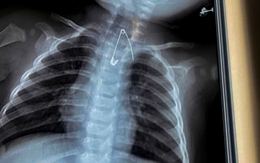

Cứu sống hai em bé nuốt kim băng và cây kẹo mút

Ngày 8-1, Bệnh viện Sản Nhi Cà Mau cho biết các bác sĩ vừa tiếp nhận và xử trí thành công hai trường hợp bệnh nhi nuốt dị vật đặc biệt nguy hiểm, trong đó có ca thủng tá tràng và ca dị vật sắc nhọn nằm sát động mạch chủ, đe dọa đến tính mạng.